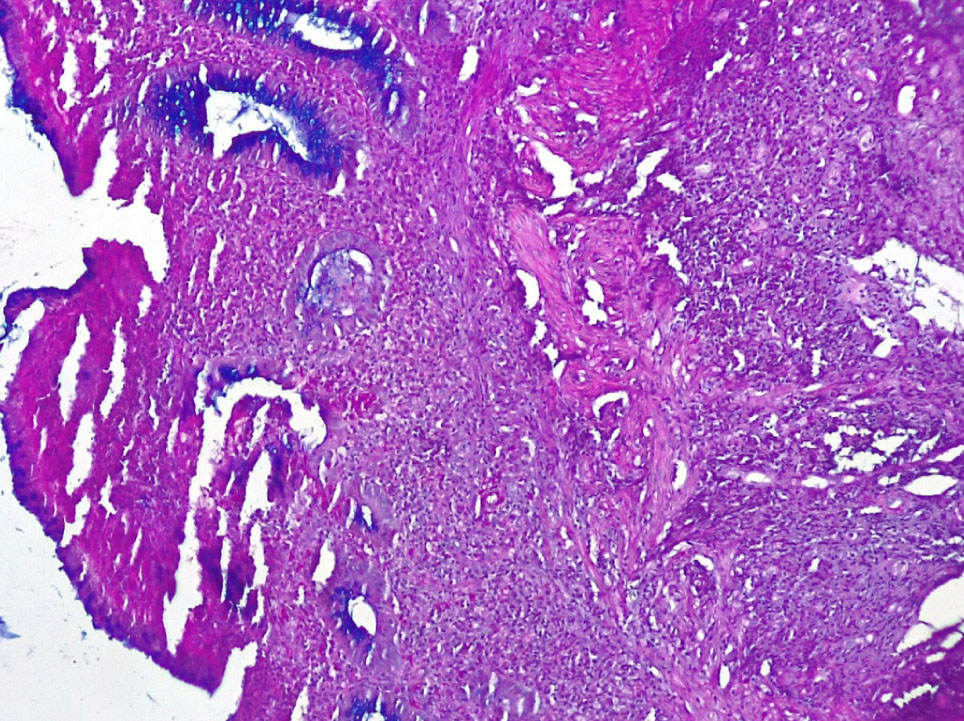

В отдельных группах крипт отмечалось выраженная атрофия бокаловидных клеток (БК) (не более 3–4 на крипту) вплоть до полного их исчезновения (+++), развитие очагов гнойного криптита за счет выраженной нейтрофильной инфильтрации вокруг крипт (рис. 4).

Рис. 4. Основная группа: неравномерная атрофия крипт и бокаловидных клеток СО толстой кишки, выраженное хроническое воспаление стромы со скоплением нейтрофилов в отдельных криптах (гнойный криптит). Окр. гематоксилин-эозином, ×200